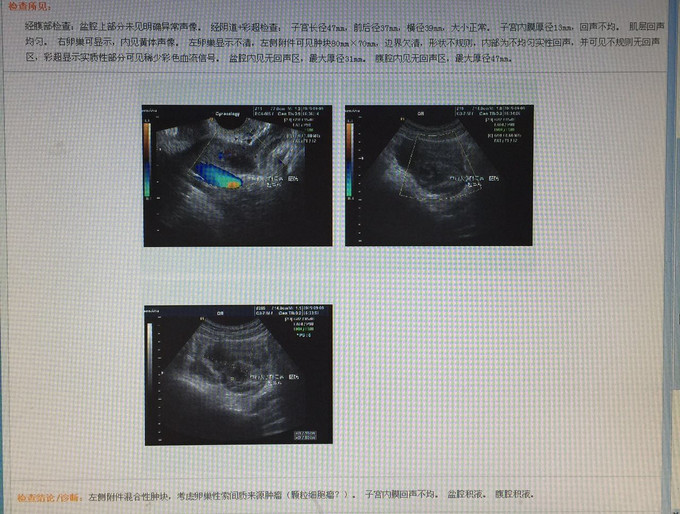

入院后予完善术前检查、盆腔、腹部泌尿系B超、心脏彩超、肺功能测定、胃镜、肠镜检查,盆腔CT、B超、胃镜、肠镜结果如图所示,余检查未见异常,肿瘤标志物未见异常。

完善术前检查后诊断:盆腔包块性质待查:卵巢癌?于9月14日行剖腹探查术。术中进入盆腔见大量积血及血块,量约400mL,左卵巢肿物1*1cm,表面光滑,有一破裂口,长约2cm,见少量活动性出血,左输卵管轻度水肿,外观未见异常,左附件与盆壁及乙状结肠表面粘连,左侧盆壁腹膜及乙状结肠系膜见粗糙面,有少量渗血,未触及明显赘生物;右卵巢表面一肿物1.5*1.5cm,表面光滑,右输卵管外观未见异常,子宫正常大小,外观未见异常。探查肝、胆、胃、胰、小肠、大肠、大网膜未发现肿瘤,腹主动脉旁淋巴洁无肿大,双侧盆腔淋巴结无肿大。予行双侧卵巢肿物剔除术,并送冰冻病理检查,结果回报:左卵巢卵巢组织,局部见出血;右卵巢黄体,局部见出血。向家属交待病情后关腹,结束手术。